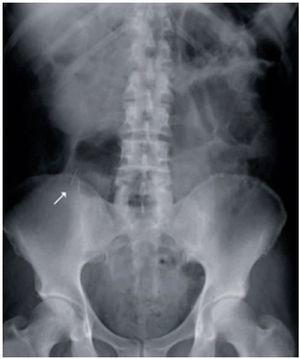

A 66-year-old man with an unremarkable past medical history was admitted to the hospital with symptoms of abdominal pain of 36-hour progression suggestive of acute appendicitis. Laboratory work-up reported: 21,500 leukocytes/cc, neutrophils 84.8%, and the remaining tests were normal. A plain anteroposterior abdominal x-ray showed the presence of 2 radio-opaque, filiform, sharp-ended, metallic objects measuring approximately 5 cm and located in the lower right abdominal quadrant (Fig. 1). During the medical interview, the patient denied having swallowed any type of foreign body in the previous days or months. The diagnosis of intestinal perforation secondary to foreign bodies versus appendicitis secondary to foreign bodies was established. Exploratory laparotomy revealed an approximately 9 cm retrocecal appendix perforated at its middle third section by the protruding tip of a straight pin, with its body and a second pin inside the appendicular lumen. Appendectomy was performed with no complications. The presence of the two foreign bodies inside the appendicular lumen was corroborated in the operating room through x-ray of the specimen (Fig. 2). The histologic report of the specimen was acute appendicitis with abscess and the presence of 2 straight pins in the lumen (Fig. 3). The patient progressed satisfactorily and was released 48 hours after surgery.

Figure 2. X-ray of the surgical specimen showing the 2 pins inside the appendicular lumen.